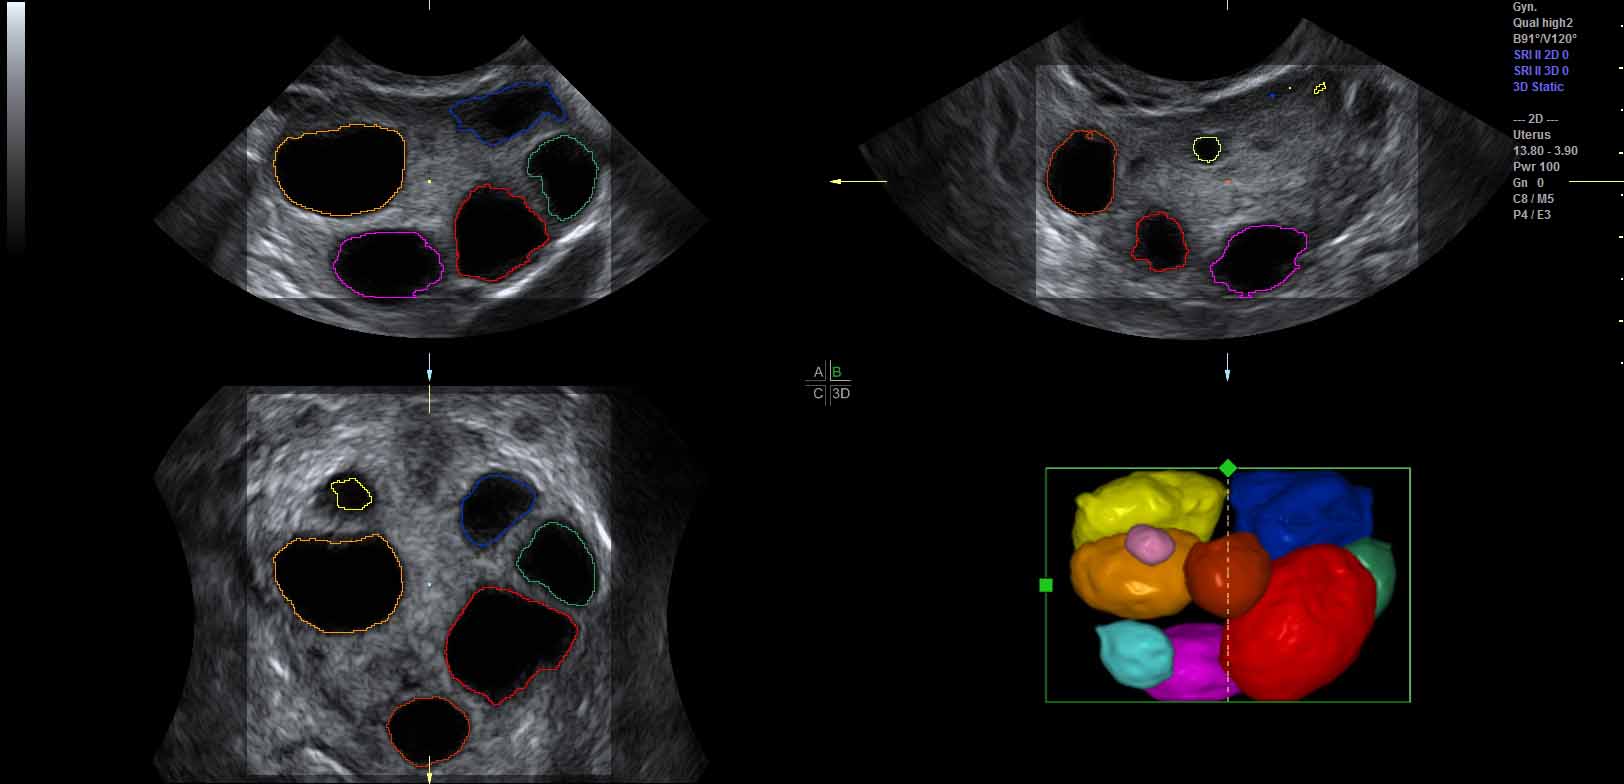

To increase robustness of the ultrasound segmentation, the various approaches are usually tailored for specific anatomies. Carneiro et al. have developed an automatic technique for segmenting the brain of a fetus carneiro08 . By first detecting the cerebellum, the system can narrow down the search for other features. On the other hand, segmentation is an extremely critical procedure which may obscure diagnostically relevant aspects of the anatomy under examination. Consequently, fully automatic segmentation techniques have not been implemented in clinical systems so far, with the exception of a method for follicle volumetry deutch09 , as shown in figure 3.

Refer to caption

Figure 3: Automatic segmentation of the ovarian follicles deutch09 .